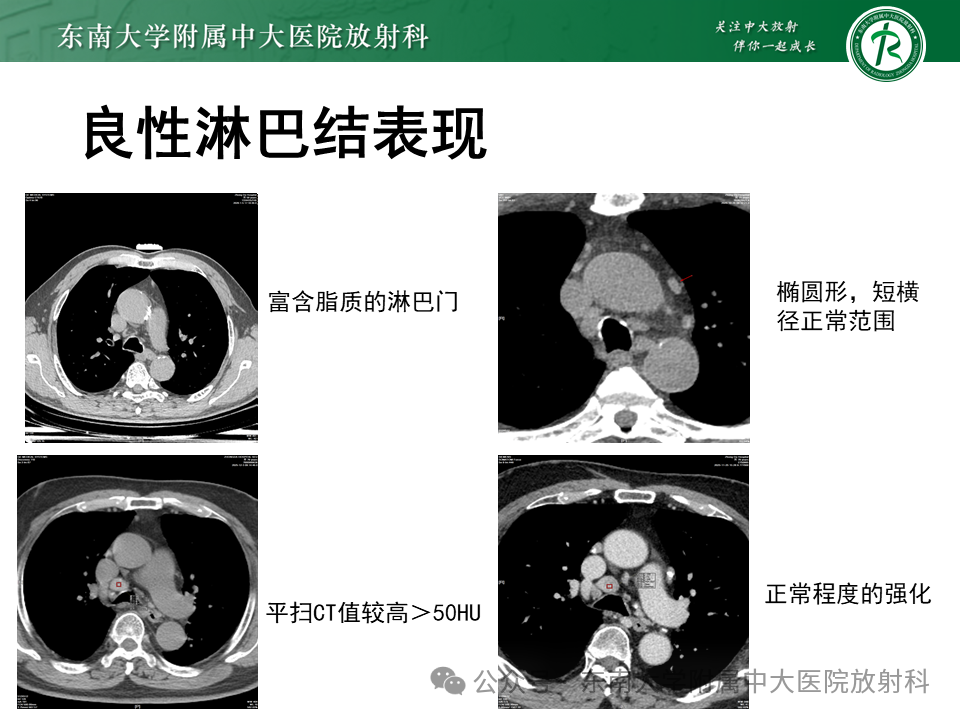

非小细胞肺癌(NSCLC)的淋巴结转移的影像评估

来源:东南大学附属中大医院放射科